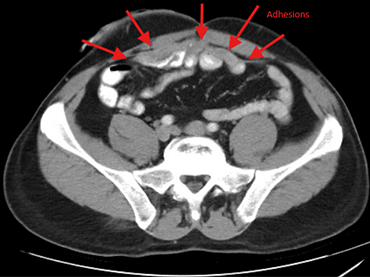

Image of scan. “The challenges of performing minimally invasive surgery on someone who had an emergent open operation are significant,” says Dr. Whelan. “They typically have a lot of scar tissue and adhesions. It can limit the ability to do minimally invasive surgery.”

The patient met Dr. Whelan on the day of his procedure. The surgeon began with a laparoscopic exploration, which showed the patient didn’t have free space in his belly.

“It was all collapsed with scar tissue, and I was able to make enough space laparoscopically that I could see,” describes Dr. Whelan.

Next, meticulous lysis of adhesions and scar tissue was needed, which can be done laparoscopically.